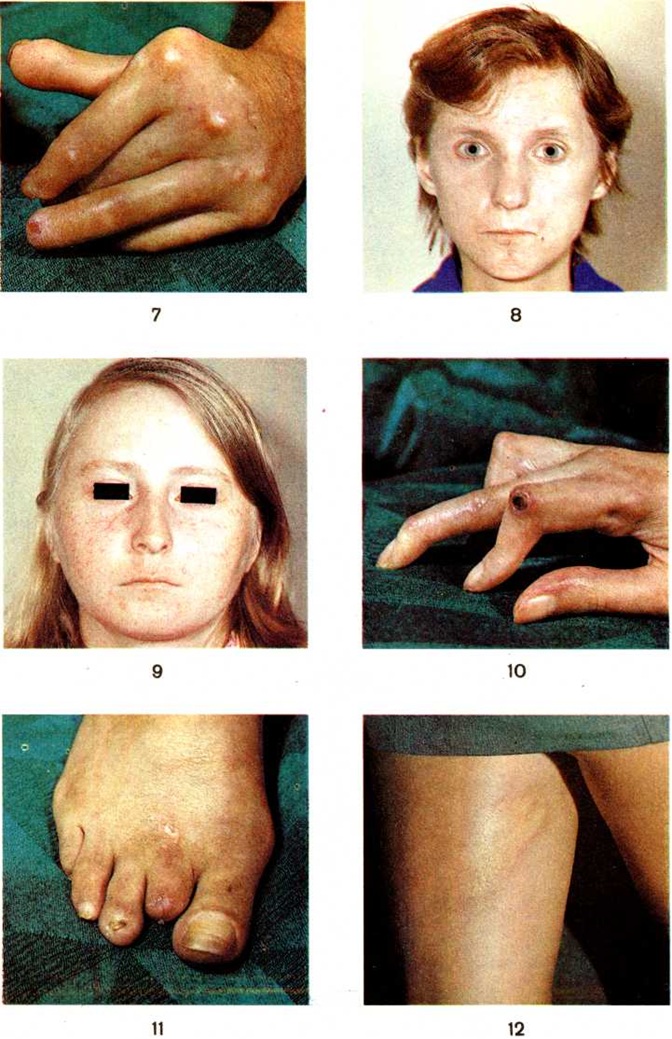

Одним из важных диагностических признаков системной Склеродермия является характерное поражение кожи, меняющее внешний облик у 80— 90% больных, но в начале заболевания наблюдающееся лишь в 1/3 случаев. Локализуется главным образом на кистях — склеродактилия (цветной рисунок 7), на лице — маскообразность (цветной рисунок 8), верхней половине туловища, стопах; реже (преимущественно при быстром прогрессирующем течении) наблюдается диффузное поражение кожи. Наряду с характерными склеродермическими изменениями кожи, проходящими стадии плотного отёка, индурации (смотри, полный свод знаний:) и атрофии (смотри полный свод знаний), отмечаются гиперпигментация, нередко чередующаяся с участками депигментации (смотри полный свод знаний: Дисхромии кожи), телеангиэктазии (цветной рисунок 9), трофические нарушения (деформация ногтей, облысение). У отдельных больных наблюдается поражение кожи по типу ограниченной Склеродермия Нередко отмечается поражение слизистых оболочек — хронический конъюнктивит (смотри полный свод знаний), атрофический и субатрофический ринит (смотри полный свод знаний), стоматит (смотри полный свод знаний), фарингит (смотри полный свод знаний) и поражение слюнных желёз, в ряде случаев синдром Шегрена (смотри полный свод знаний: Шегрена синдром).

Синдром Рейно — ранний и частый признак системной Склеродермия, встречается, по данным различных исследователей, у 70—90% больных. В отличие от болезни Рейно, синдром Рейно при системной Склеродермия более распространённый: изменение сосудов отмечается на кистях, стопах, иногда в области лица, аналогичные изменения — в лёгких и почках. Нередко синдром Рейно задолго предшествует суставным и кожным проявлениям или развивается одновременно с ними. Такие факторы, как охлаждение, вибрация, эмоциональная лабильность, усугубляют уже имеющиеся нарушения микроциркуляции, способствуют прогрессированию синдрома Рейно и возникновению сосудисто-трофических изменений (цветной рисунок 10) — повторных изъязвлений тканей кончиков пальцев вплоть до развития гангрены (смотри полный свод знаний).

Характерны изменения костей в виде остеолиза (смотри полный свод знаний), чаще дистальных (ногтевых) фаланг, что проявляется клинически в виде укорочения (цветной рисунок 11) и деформации пальцев рук и ног. Для системной Склеродермия характерен кальциноз мягких тканей, известный как синдром Тибьержа — Вейссенбаха. Отложения солей кальция локализуются преимущественно в области пальцев рук и периартикулярно — вокруг локтевых, плечевых и тазобедренных суставов, в подкожной клетчатке, иногда по ходу фасций и сухожилий мышц. Кальцификация тканей развивается постепенно, как правило, не ранее чем через 5 лет от начала болезни. Чаще кальциноз тканей не вызывает неприятных ощущений и выявляется лишь рентгенологически, а при локализации его в пальцах — по деформации последних. При более бурном, чаще по типу отдельных обострений, развитии процесса выявляется инфильтрация тканей с выраженным болевым синдромом, ухудшением общего состояния и иногда лихорадочной реакцией. При поверхностном расположении очаги кальциноза могут вскрываться с выделением белой крошковатой или жидкой массы.

Бляшечная Склеродермия (sclerodermia placata) наблюдается наиболее часто. Она развивается обычно постепенно, без видимых причин, имеет длительное течение с периодами обострений и ремиссий. Характеризуется образованием на боковой поверхности туловища, спине, пояснице или проксимальных отделах конечностей одного или нескольких пятен различной величины, овальной или неправильной формы розоватого цвета с различными оттенками (лиловый, сиреневый). Пятна постепенно увеличиваются в размерах, и через несколько недель в их центральной части развиваются склеротические изменения, вследствие чего образуется гладкая плотная, как картон, блестящая, цвета слоновой кости бляшка, несколько выступающая над уровнем окружающей кожи (цветной рисунок 12). На периферии бляшки имеется фиолетового цвета зона в форме кольца, постепенно переходящая в нормальную кожу. Эта зона свидетельствует о прогрессировании процесса. Сформировавшаяся бляшка медленно увеличивается в размерах, на ней могут образовываться участки пигментации и телеангиэктазии. В редких случаях отмечаются множественные очаги поражения (генерализованная или диссеминированная бляшечная Склеродермия). Через несколько лет очаг поражения незаметно рассасывается и подвергается атрофии, оставляя слегка пигментированное западение кожи. Атрофированная кожа, напоминающая смятую папиросную бумагу, легко собирается в складку. Крайне редко в области бляшек возникают пузыри с геморрагическим содержимым(буллезно-геморрагическая бляшечная Склеродермия) или участки поверхностного изъязвления. Разновидностями бляшечной Склеродермия являются поверхностная ограниченная Склеродермия, при которой на коже развиваются небольшие темно-окрашенные пятна с лиловатым оттенком без признаков уплотнения и инфильтрации, а также узловатая форма (туберозная, келоидоподобная) в виде выступающих узлов. В зоне склеродермических бляшек выпадают волосы, снижается секреция сальных и потовых желёз.